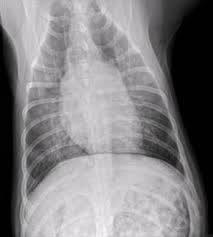

The vet will look for nasal discharge, coughing, take the temperature of the dog, and listen to the lungs using a stethoscope. Severe symptoms in combination with poor appetite could. A veterinarian will perform a full physical examination on a dog after an owner notes symptoms that are characteristic of pneumonia. But in some rare cases, it may be a lung cancer (primary or secondary). Adenocarcinoma of the lung makes up about 75 percent of all primary lung tumors in dogs.

Types Treatments Symptoms Of Lung Cancer In Dogs Plains Veterinary Oncology Northeast Veterinary Referral Hospital from d2zp5xs5cp8zlg.cloudfront.net Lung cancer is sometimes found this way. Symptoms of lung cancer are coughing (which may also produce phlegm or blood), exercise intolerance (lethargy), weight loss or loss of appetite, and other respiratory signs such as trouble breathing or shortness of breath. Antibiotics may be prescribed to treat pneumonia. A veterinarian will perform a full physical examination on a dog after an owner notes symptoms that are characteristic of pneumonia. Usually, this is a sign of your dog's body fighting the infection, but if your dog overheats, it could be dangerous or even fatal. Some severely affected dogs may have extreme exercise intolerance. Sometimes, people with pneumonia may have symptoms similar to lung cancer. However, primary lung cancers are being seen more frequently over the last 20 years.

Just like pneumonia in people, pneumonia in dogs is a serious health condition and. Usually there are no symptoms in the early stages of canine lung cancer. There are times when coughing may mean your dog has lung cancer. Most primary lung tumors are diagnosed at an average age of 10 to 12 years in dogs. A veterinarian will perform a full physical examination on a dog after an owner notes symptoms that are characteristic of pneumonia. These signs are not specific for bronchitis and can also be seen with many other diseases including heart failure, pneumonia, allergic lung disease and lung cancer. Adenocarcinoma of the lung in dogs. It is characterized by a moist, bubbling cough and fever. However, primary lung cancers are being seen more frequently over the last 20 years. Some of the pneumonia symptoms overlap with those of the cold, but the condition also has discerning symptoms of its own. Primary lung tumors average cost. It usually results in mild symptoms, mild or no pneumonia, and it resolves within 5 to 7 days. Sometimes, people with pneumonia may have symptoms similar to lung cancer.

Lung Cancer In Dogs Causes Signs Treatment Canna Pet from g77v3827gg2notadhhw9pew7-wpengine.netdna-ssl.com Primary lung tumors, also known as pulmonary tumors, are frequently malignant and require surgery to remove both the growth and a significant portion of the lung. Pneumonia in dogs can have different causes: It usually results in mild symptoms, mild or no pneumonia, and it resolves within 5 to 7 days. Melanomas in dogs tend to affect the mouth and lips, and they can also be found on their nail beds, footpads and eyes. Pneumonia is a common lung infection. Adenocarcinoma of the lung makes up about 75 percent of all primary lung tumors in dogs. Sometimes, people with pneumonia may have symptoms similar to lung cancer. If your dog's pneumonia progresses without responding to treatment, your vet may recommend more extensive diagnostics to get to the root of the problem.

The cause can be bacteria, a virus, or fungi. Symptoms of primary and metastatic lung cancer are similar, although dogs with metastatic disease don't cough as much, according to the merck veterinary manual. It is also possible that a cancer diagnosis can be delayed if the cancer is mistaken for pneumonia. Unlike some other types of cancer, there are some concerning symptoms that arise in the earlier stages of primary lung cancer for dogs that should immediately alert you that something is wrong. Most primary lung tumors are diagnosed at an average age of 10 to 12 years in dogs. When they do cough, they might bring up blood. Pneumonia in people with lung cancer. It is caused by a viral or bacterial infection in the respiratory tract. Primary lung tumors average cost. Lung cancer is sometimes found this way. Canine distemper virus, adenovirus types 1 and 2, canine influenza virus, and. Some of the symptoms may include: Some of the pneumonia symptoms overlap with those of the cold, but the condition also has discerning symptoms of its own.